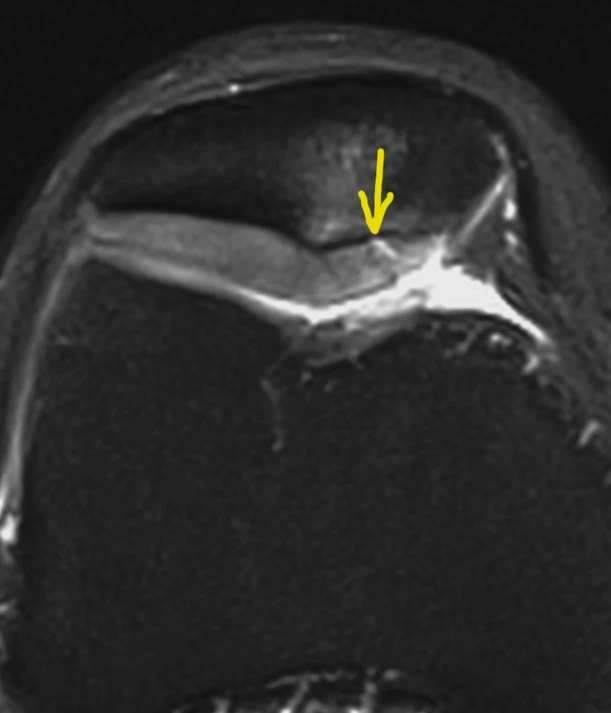

Обширная, ветвистая венозная мальформация (ранее известная, да и до сих пор тоже, как гемангиома) мягких тканей области коленного сустава.

Картина типичная, дифференциальная диагностика не требуется.

Представляет собой скопление аномальных, расширенных, извитых венозных сосудов, стенка которых гистологически не отличается от стенок обычных вен. Хорошо видны связи мальформации с обычными венами. Внутри некоторых из полостей видны выпадение сигнала, которые являются флеболитами (кальцинированными внутрисосудистыми тромбами).

Кстати, может никак не проявляться клинически, будучи даже таких больших размеров.